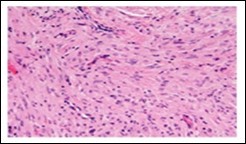

Figure 3.Soft tissue perineurioma with whorls and fascicles of neural cells displaying wavy nuclei, elongated cytoplasmic fibrils and intermingling of collagen fibres 13.

Figure 4.Soft tissue perineurioma composed of whorls and perivascular aggregates of neural cells with bipolar cytoplasmic processes, wavy, slender nuclei and commingled collagen fibres 13.

The neoplasm can depict perivascular whorls. Mitotic activity can be observed enumerated as 0-13 /30 high power fields, although around 65% tumours are devoid of mitotic activity. Neoplasms of extensive duration can exhibit foci of degenerative atypia with modifications such as nuclear pleomorphism and nuclear hyperchromasia with intracytoplasmic and intra-nuclear inclusions. Tumour necrosis is generally absent5, 6. Microscopically, a perineurioma composed of bland, ovoid to spindle-shaped cells with elongated, slender nuclei and elongated, bipolar cytoplasmic processes can delineate a storiform, lamellar or a whorled pattern or perivascular aggregates of neoplastic cells are configured, disseminated in a collagenous or focally myxoid stroma. Lesions such as a hybrid schwannoma or perineurioma with features intermediate betwixt a schwannoma and perineurioma can be discerned. Characteristically, bland, ovoid to thinly elliptical, spindle-shaped cells with elongated, delicate, bipolar, cytoplasmic processes are exemplified with a storiform or whorled architectural pattern. Intervening stroma can be myxoid, collagenous or myxo-collagenous5, 6.